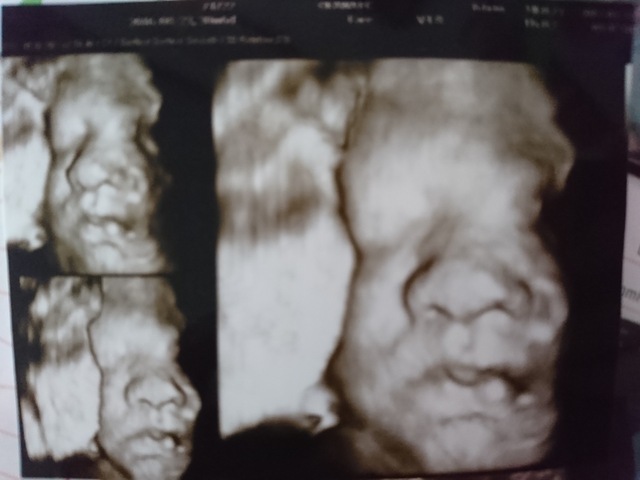

30週4日(30w4d・女の子)|ぴっっっと さん(29歳)

エコー写真撮影時のエピソード:

お分かりいただけただろうか…

とホラー番組のナレーションがありそうなお顔が撮れました。

女の子なのに、パパ似で丸い顔、大きな鼻、厚いくちびる、岩のような顔でこちらを見ています。。

ちなみに28週の4Dエコーでは、びっしり生えた剛毛と太くて短い脚が映っていました。

先生からは、この週数でしっかり髪の毛がありますね!と謎のフォローを頂きました。